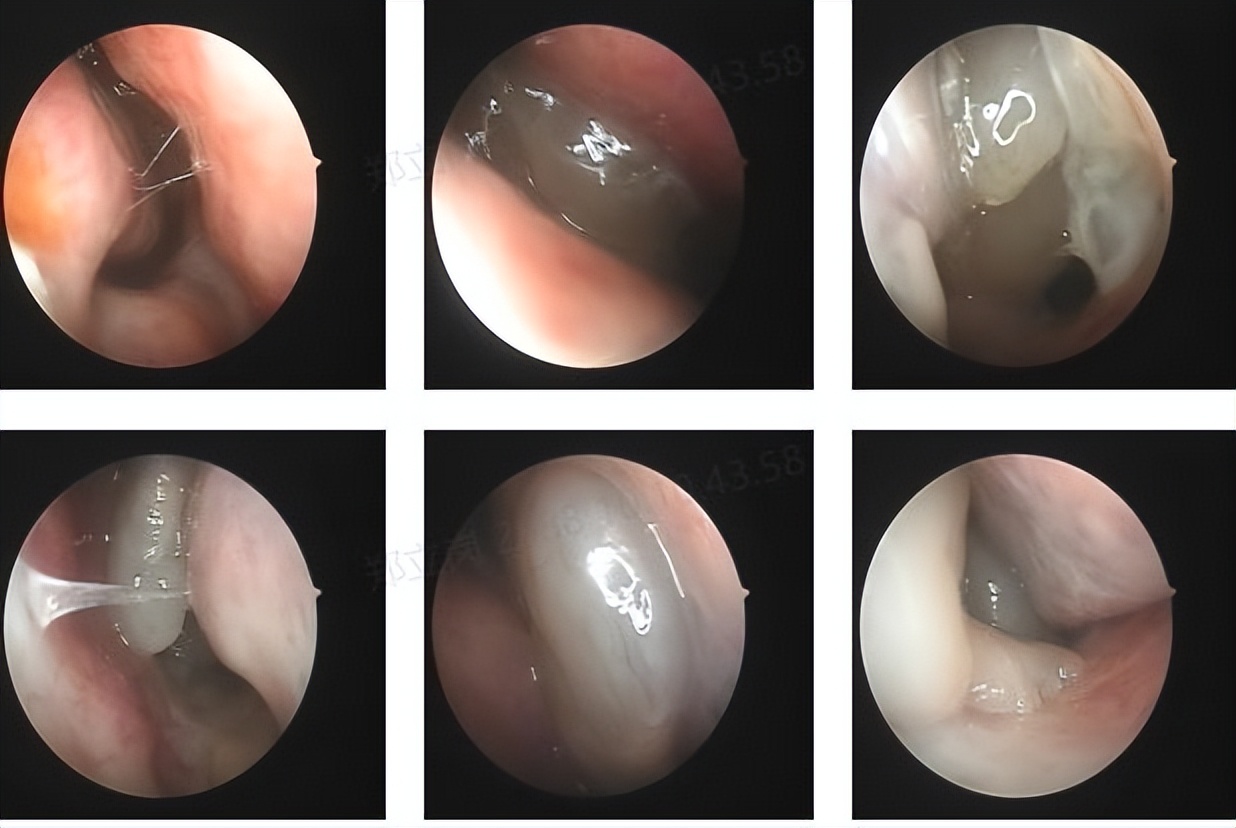

门诊鼻内镜检查提示:鼻窦炎伴鼻息肉。10年前曾在佛山第二人民医院行"鼻内镜鼻息肉切除+鼻中隔偏曲矫正手术"。但这次是明显的复发了,需要再次的手术治疗。

这次做了全麻鼻内镜鼻息肉切口鼻窦开放术,手术做的非常的顺利。但该手术术后需要进一步的治疗鼻炎,术后也对患者的鼻炎做了相应的治疗,再加上术后的治疗,只要鼻炎控制的好,一般复发的可能就会明显的减少。